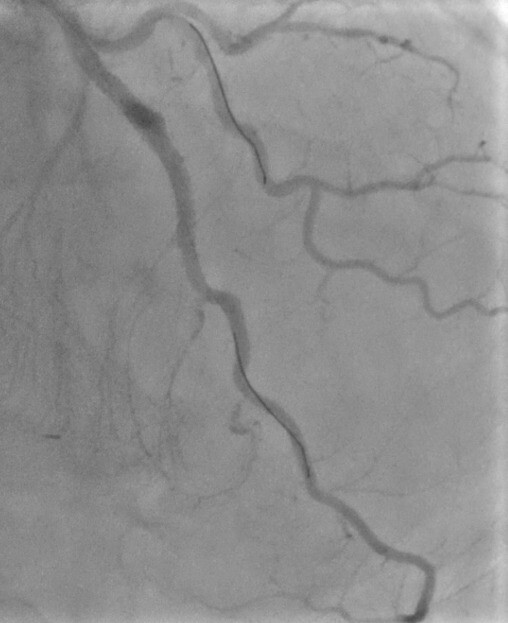

A man in his 70s was admitted with a three-week history of crescendo angina that culminated in prolonged chest pain at rest. Relevant past medical history included a transient ischaemic attack, five myocardial infarctions (MI), with a first CABG performed in 1985 with SVG to the left anterior descending (LAD), left circumflex (LCx), and right coronary (RCA) arteries and a subsequent further bypass surgery in 2005 with LIMA to LAD and SVGs to RCA and first obtuse marginal arteries. He was a non-smoker, independent with activities of daily living and not limited by exertional symptoms prior to this presentation. His medications included ramipril 2.5 mg twice daily (bid), lansoprazole 15 mg once daily (od), isosorbide mononitrate 60 mg od, eplerenone 25 mg od, dapagliflozin 10 mg od, bisoprolol 5 mg od, aspirin 75 mg od, and atorvastatin 80 mg od. Physical examination was unremarkable apart from a prior sternotomy scar, and moderate left ventricular systolic dysfunction was noted on trans-thoracic echocardiography. His electrocardiogram (ECG) showed sinus rhythm with a left bundle branch block, unchanged from 2014. High-sensitivity troponin was elevated but remained static 31 ng/L (99th percentile values less than 15 ng/L). The remainder of the blood tests were unremarkable. Angiography was performed in a local district general hospital, which showed that the LAD and LCx arteries had chronic total occlusions (CTO), and the SVG to LAD, performed in the initial bypass procedure, had severe disease with sluggish flow (figure 1). The LIMA to the LAD, performed in the second bypass procedure, had completely occluded as well, likely secondary to competitive flow from the previously functioning SVG to the same artery. The RCA had diffuse severe disease with a complete mid-vessel occlusion, while the SVG to posterior descending artery (PDA) was patent. Similarly, the SVG to obtuse marginal (OM) branch was also patent. An attempt at revascularisation of the diseased SVG to LAD was performed locally, but was unsuccessful, and, therefore, the patient was referred to our centre for further management of ongoing ischaemic symptoms.

Given his rapidly progressive symptoms, it was decided to proceed with a further invasive angiogram with a view to revascularisation, instead of opting for non-invasive stress tests. A 6 French (Fr), Amplatz left 3.0 (Medtronic, Ireland) guide catheter was used to engage the SVG to LAD. Although both Confianza and Gladius guidewires were able to negotiate the vessel stenosis, multiple attempts at crossing with balloon or microcatheter were unsuccessful. Due to prolonged procedure time, it was decided to stop the attempt and consider a further review in a multi-disciplinary meeting, as well as with the patient and his preferences. On review of angiography images, a potential antegrade channel was identified in the LAD CTO and, given significant ongoing symptoms, it was decided with the patient to have a further attempt at revascularisation of the native chronically occluded LAD artery, instead of medical therapy, given the severity and persistence of chest pain, accepting a higher risk of potential complications. Therefore, a 7 Fr sheath was inserted, using ultrasound guidance, into the right femoral artery to allow improved guide support and 10,000 units of unfractionated heparin administered, with a further 5,000 units given subsequently, to maintain activated clotting time of greater than 250 seconds. Given the patient had patent SVGs to PDA and OM vessels and moderately impaired left ventricular systolic function, mechanical support would not have offered additional benefit, and would have exposed the patient to an additional risk of complications. Therefore, a 7 Fr XB 3.5 guide catheter (Cordis, UK) was used to engage the coronary ostium and a Sion (Vascular Perspectives, Holmfirth, UK) guidewire assisted by a Turnpike (Teleflex, US) microcatheter was used to negotiate the stenosis. Attempts at crossing the lesion with a balloon were, again, unsuccessful. Therefore, the workhorse wire was exchanged for a rota-floppy wire (Boston Scientific) and rotational atherectomy, using a 1.5 mm burr, was performed, which was successful in crossing the mid-CTO artery (figure 2). The Sion wire was reintroduced, and pre-dilatation of the mid-LAD was performed using a 2.5 × 12 mm semi-compliant balloon, followed by a 3.0 × 20 mm non-compliant (NC) balloon at 16 atmospheres (ATM), successfully restoring blood flow (figure 3). Since the NC balloon expansion was satisfactory and allowed good estimation of the reference target vessel measurements, it was opted to proceed with stent deployment at the mid-proximal (3.0 × 20 mm Supraflex, SMT, India) and mid-LAD (3.0 × 32 mm Supraflex, SMT, India) at 14 ATM with good apposition and absence of edge dissection (figure 4), and excellent flow post-stent placement (figure 5).